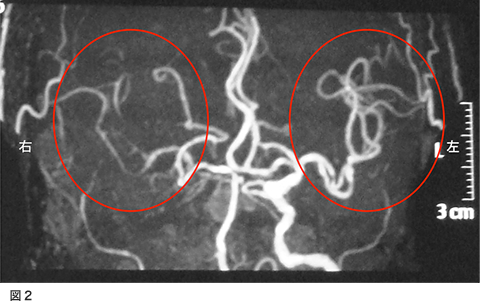

脳梗塞で発症された方です。意識障害と左不全片麻痺、構音障害で発症されました。図1が入院時のMRI拡散強調画像です。右側の白くなっているところが脳梗塞になっている部位です。図2の、MRA(MRIで行う血管の検査)では、右側の中大脳動脈の描出がほとんど無い状態でした。